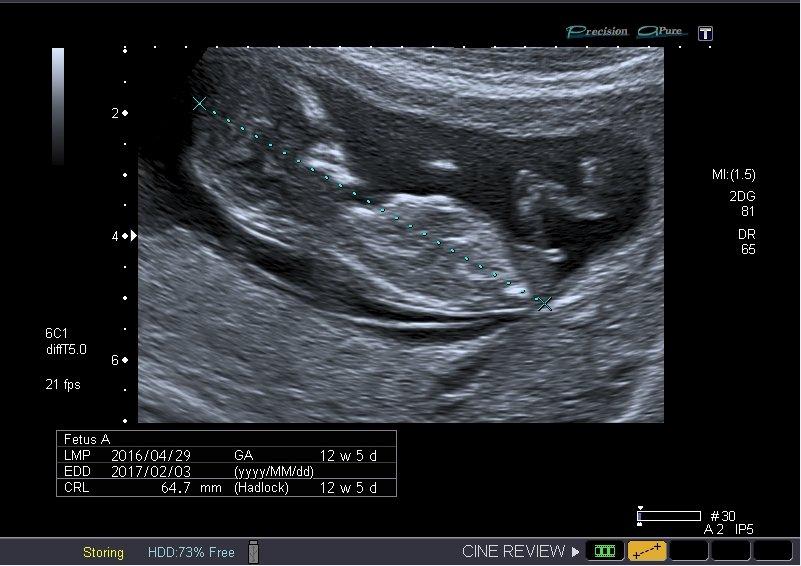

Z tohto to pozna len spickovy odbornik na prenatalnu diagnostiku, povedala by som, ze vlastne ani ten nie z tohto snimku. Pri urcovani pohlavia v tomto tyzdni sa posudzuje uhol pohlavneho hrbolu ci ako sa to vola....a na to treba super oko a skvely pristroj. Takze bohuzial musis si par tyzdnov pockat, od nikoho tu sa odpoved nedozvies.

@operetka Mě bylo řečeno, že v tomhle týdnu vypadají všichni jako chlapečci, že se to poznat nedá..a když, tak je to jen odhad.